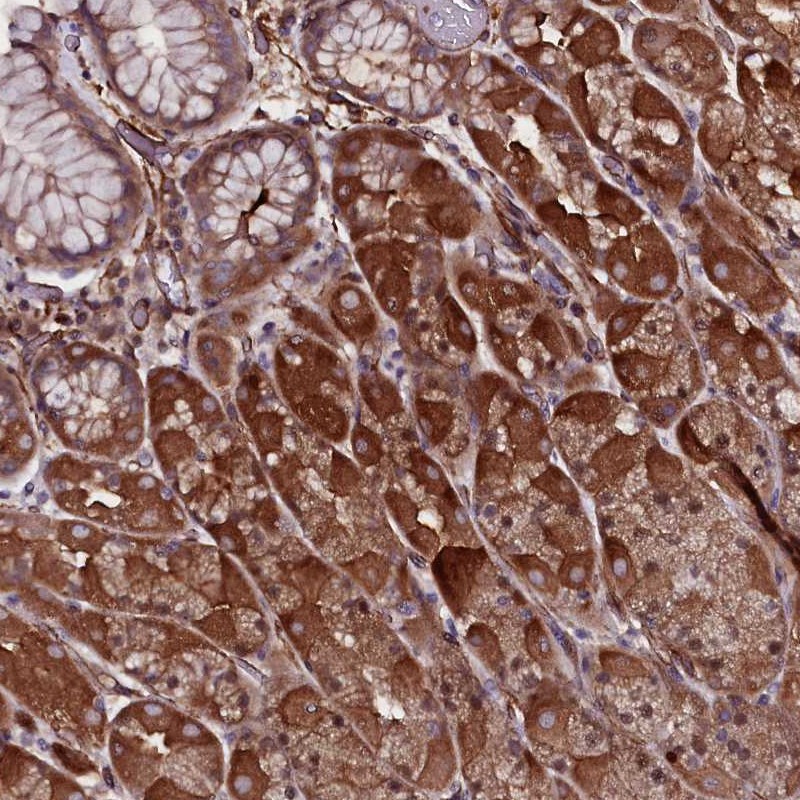

Immunohistochemical staining of human stomach shows strong cytoplasmic positivity in glandular cells.